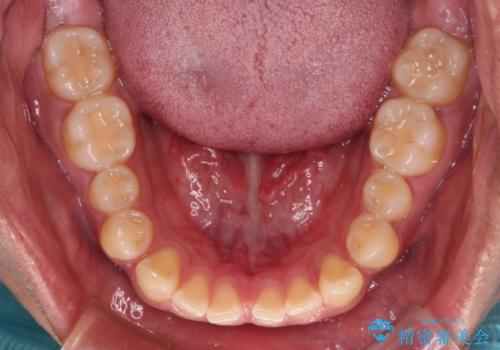

- 上下前歯の隙間を気にして来院された患者様です。

飲み込みや話をするときに舌を突出させる癖が強くあり、それが原因でスペースが空いていました。

舌癖を改善するためのトレーニングを行いながら、ワイヤー装置を用いて前歯の隙間を閉じていくこととしました。